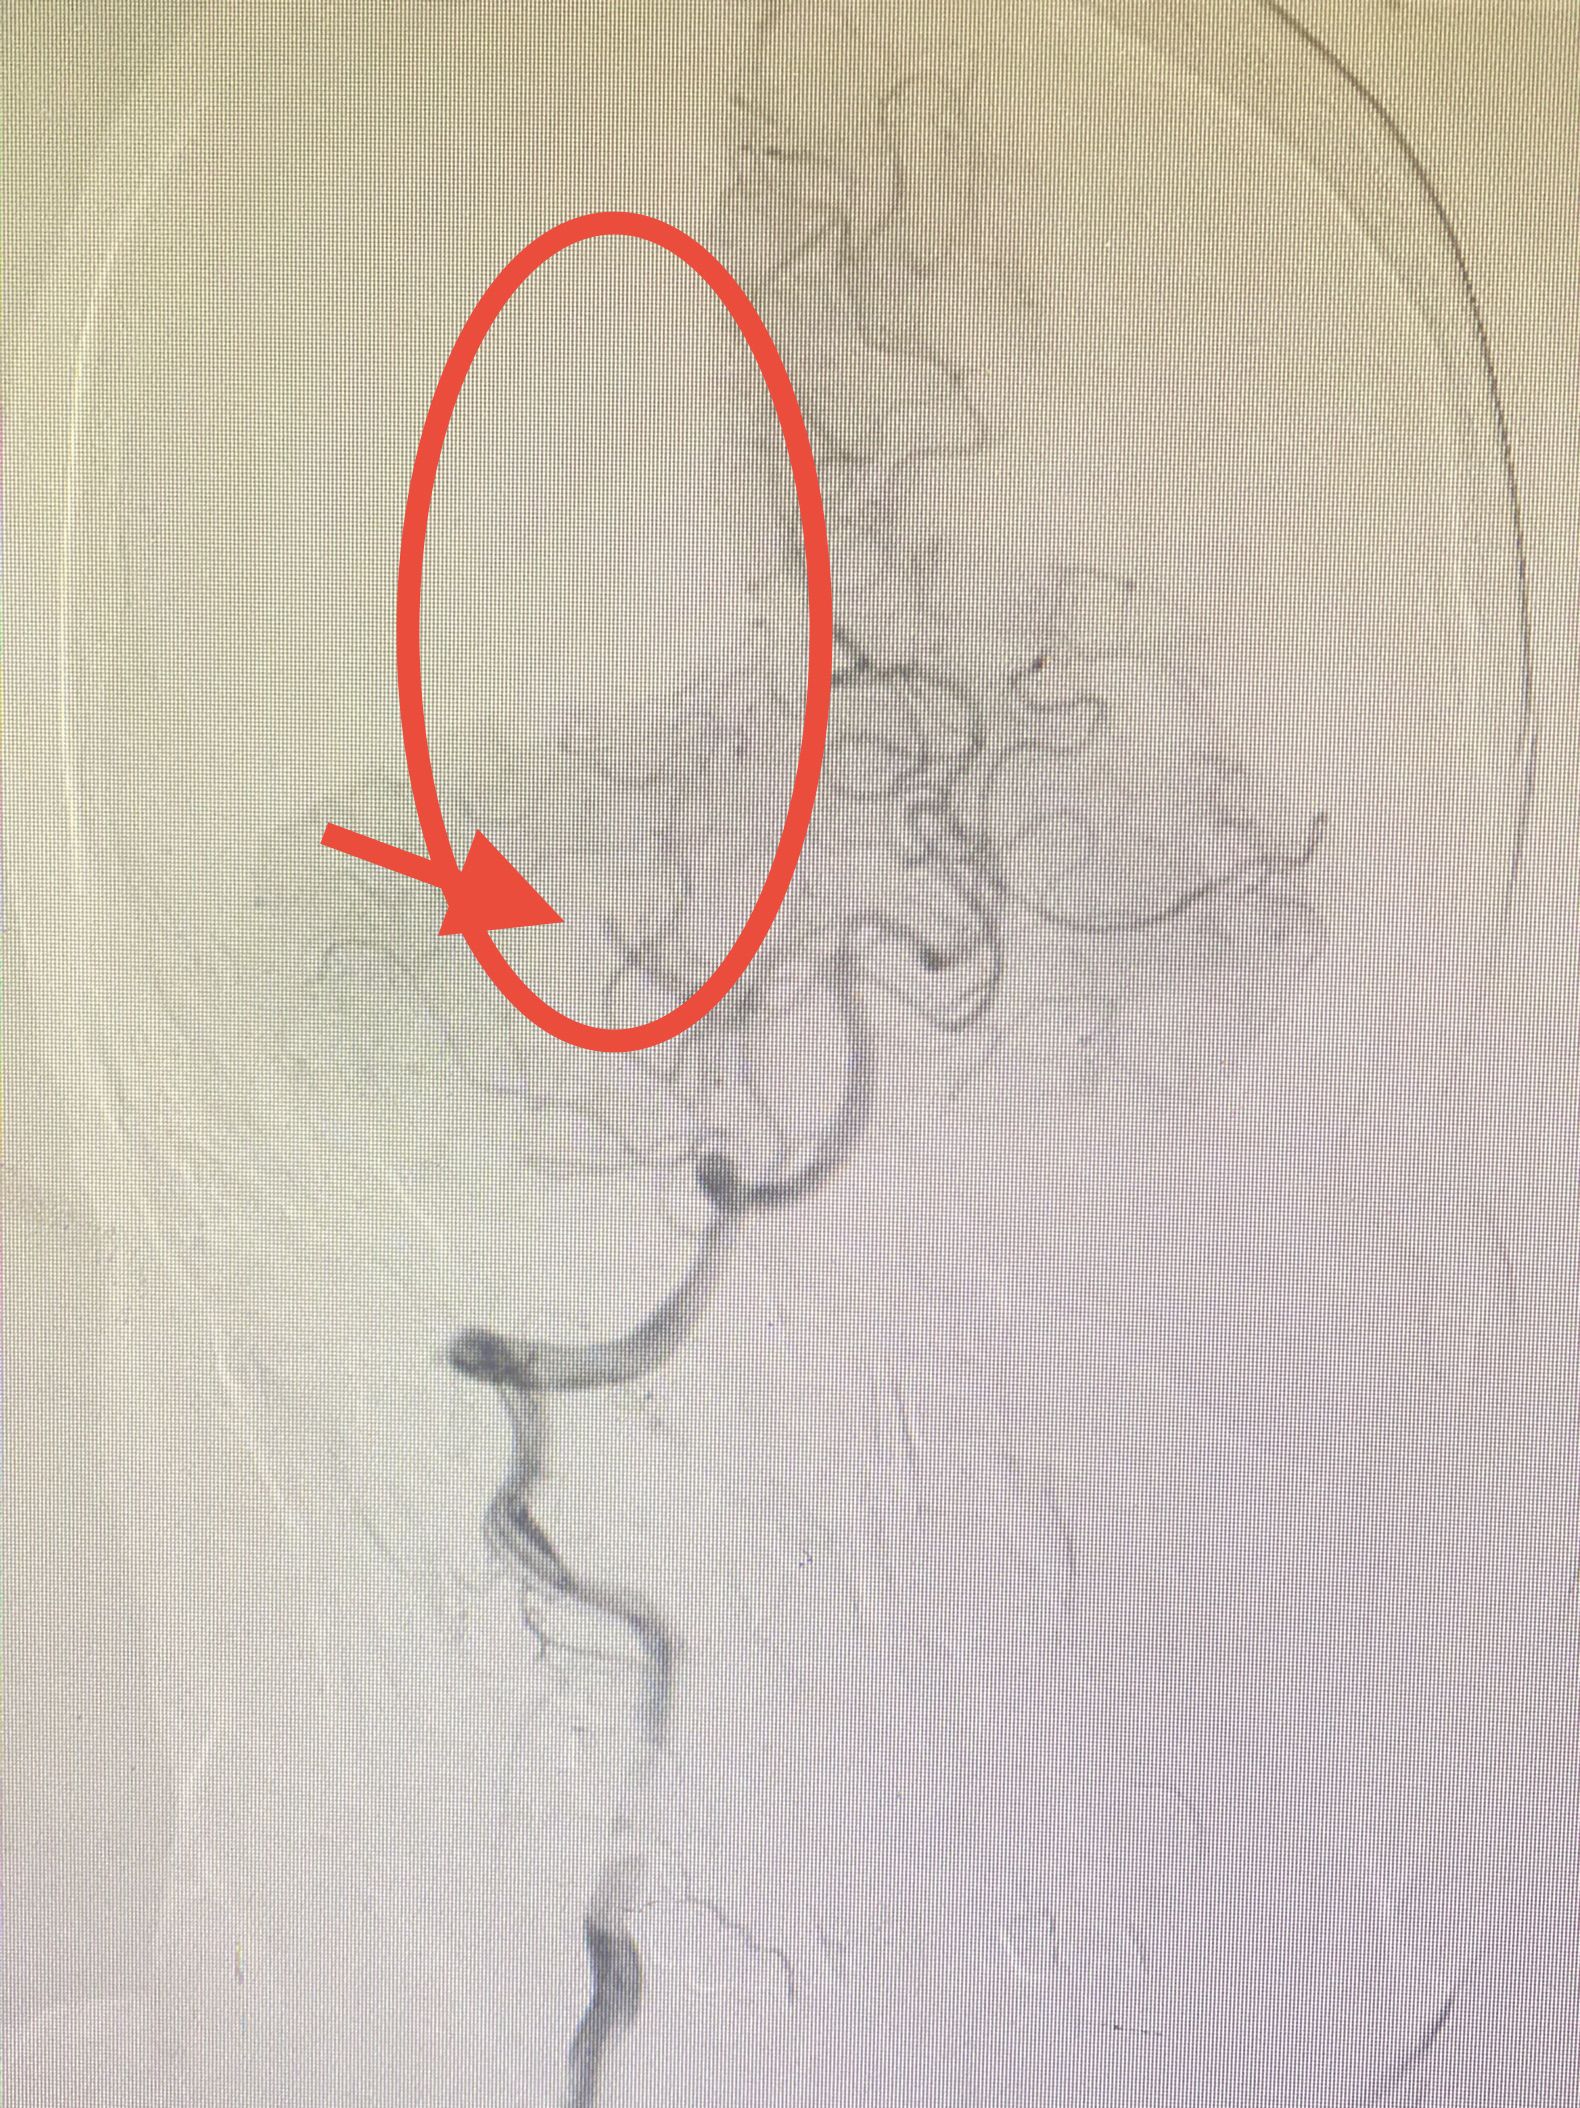

患者王某,女,66岁。因“突发左侧肢体麻木伴左侧忽视6小时”主诉入院,查体:神志清,左侧肢体痛觉减退,左侧肢体认识不能。NIHISS评分:3分。急诊头颅核磁共振DWI序列提示:右侧丘脑新发梗死灶(图1),MRA提示右侧大脑后动脉闭塞(图2)。

图2:右侧大脑后动脉闭塞(红箭)

神经内科介入组立即开通绿色通道,5分钟完成造影检查,造影见:右侧大脑后动脉闭塞,闭塞残端杯口状,局部可见血栓影,考虑血栓栓塞。(图3)

图3:右侧大脑后动脉闭塞(红箭),远端无血流(红圈)